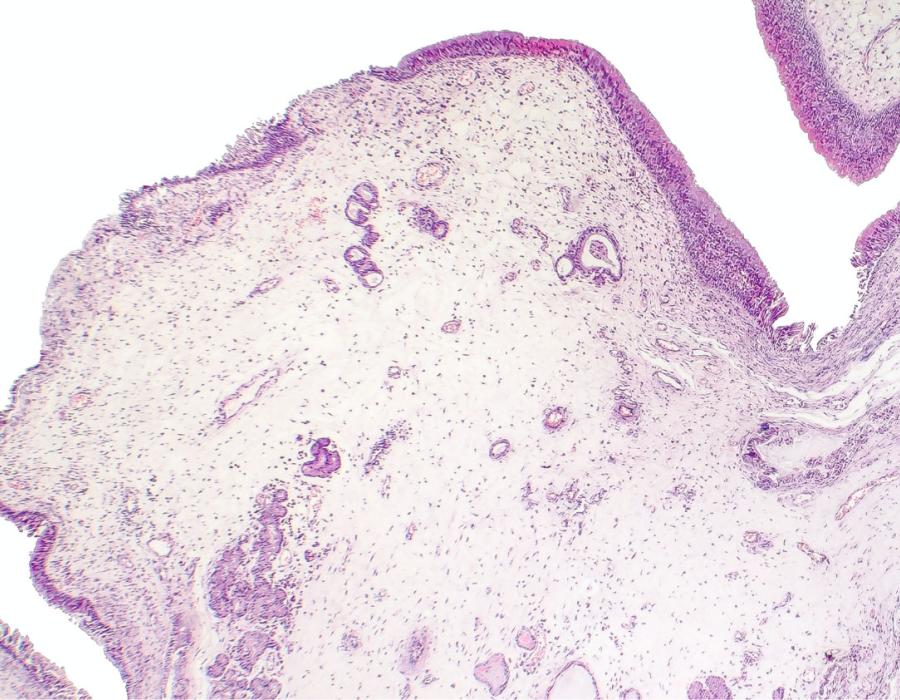

Polyps are tissue growths inside the colon or rectum that are generally benign but can develop into cancer if they are allowed to grow. Some types of polyps can change into cancer over time (usually many years), but not all polyps become cancer. The chance of a polyp turning into cancer depends on the type of polyp it is.

There are three different types of polyps that can be found inside the colon or rectum with colonoscopy2:

- Hyperplastic polyps and inflammatory polyps: Most common polyps, generally not pre-cancerous.

- Adenomatous polyps (adenomas): Can change into cancer and because of this are called a pre-cancerous condition.

- Sessile serrated polyps (SSP) and traditional serrated adenomas (TSA): Often treated like adenomatous polyps and removed during a colonoscopy because they also have a high risk of developing into colorectal cancer